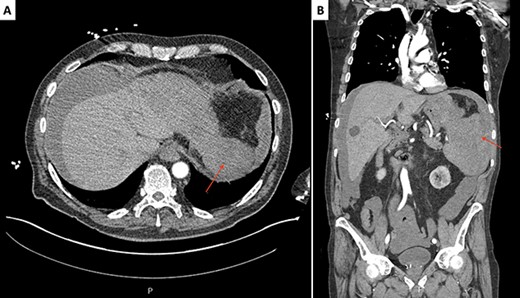

Electrocardiogram showed sinus tachycardia (113 beats/minute). Computed tomography (CT) angiography of the chest, abdomen and pelvis was remarkable for splenomegaly and a large ruptured splenic subcapsular hematoma with moderate hemoperitoneum (Fig. 1). No potential vascular source of hemorrhage or masses were identified. He was initiated on a massive transfusion protocol with five units of packed red blood cells and two units of fresh frozen plasma. He received a dose of piperacillin–tazobactam and underwent emergent exploratory laparotomy with splenectomy. Intraoperative findings included a large hemoperitoneum with 3 l of dark blood around the spleen. The spleen was ruptured with a very large, separated capsule from the hematoma. Postoperatively, he developed a productive cough, with a left basilar opacity on X-ray, managed with antibiotics. He was eventually discharged with hematology/oncology outpatient follow-up.

Initial CT scan of the abdomen and pelvis, axial (A) and coronal (B) slices, revealing a splenomegaly and a large ruptured supcapsular splenic hematoma (red arrows).